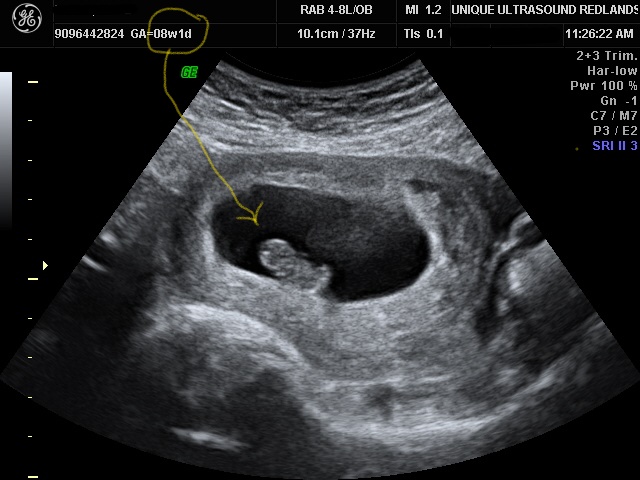

Let's talk about placentas. This organ grows along with your baby in your womb and connects the baby to your bloodstream. It carries nutrients to the baby and takes away baby's waste. The placenta also produces hormones, including one called human chorionic gonadotropin, or HCG. This is the hormone that make you miss your period. While the placenta keeps some substances in your blood from entering your baby's circulation, it doesn't keep every harmful substance away from your baby. So, the earlier you know you are pregnant, the sooner you can pay special attention about what goes into your body! That’s why we offer a First Look Ultrasound starting at just five weeks!

Remember Mom, your body is growing a little human and even though we get to experience seeing these little miracles everyday, it still amazes me!

Book an appointment now to see your new little one by clicking here. Or call us at (951) 703-3087.